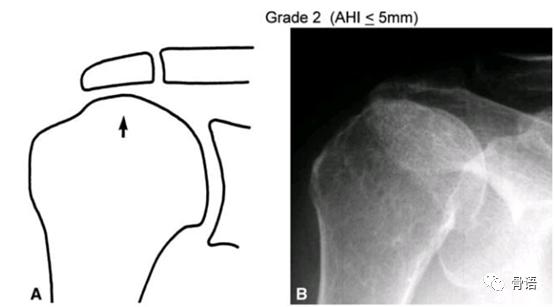

日本骨科医生东海大学浜田一寿(Kazutoshi Hamada)描述了巨大肩袖撕裂在X线上的影像学表现。Hamada分型对评估肩关节肩袖撕裂程度及骨性关节炎的程度具有重要的指导意义。可以指导我们是否需要进行肌腱转位手术或反式全肩关节置换术。

Grade2:肩峰和肱骨头之间的间隙≤5mm。